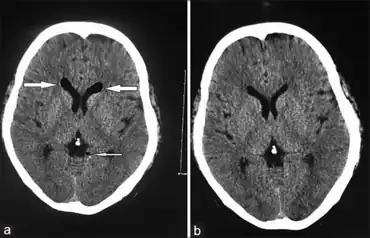

| Inadvertent epidural puncture causes Thunderclap headache-a)Air collection in frontal horns of lateral ventricles b) fairly normal one month later | |